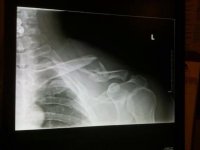

Me and my family Dr. were out in the Freemont area going from the Husky Monument over to inscription canyon. He fell and broke his collarbone. Had to ride his bike the 25+ miles back to the truck. On the way home he's making phone calls. We get home at 5:00, he's getting wheeled into the OR at 8:00 and in recovery at 1:00am. 17 screws and a plate later....